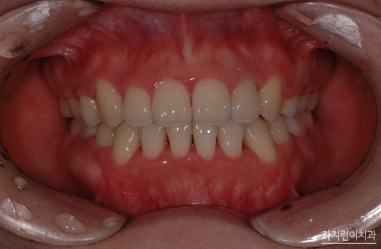

무조건 발치를 진행하지 않아도 되는데요. 치아 사이의 법랑질을 약간 삭제해 공간을 얻는 치간삭제 방법이나, 전악후방 이동이나, 악궁확장 등의 방법으로도 공간을 확장해볼 수 있습니다. 물론 비발치교정이 불가능한 경우도 있기 때문에 각도나 위치에 따라 발치가 필요한 경우도 있는데요. 그런 경우에는 고집 피우지 않고 설계한 플랜대로 발치를 진행해 공간을 충분히 두고 교정을 해두는 게 좋습니다.

한마디로 덧니교정은 성장기에 진행해도 좋지만 성인이 된 이후에도 받아볼 수 있는데요. 덧니로 인해 불편함이나 구강질환이 걱정된다면 바로 치아교정을 시작하는 게 좋겠습니다. 덧니 교정이라고 해서 부분교정으로만 극복할 수 있는 것은 아닌데요. 덧니 형태와 전체적인 치열 상태를 확인한 후 구강 구조와 골격 등을 살펴 플랜을 수립해야 하겠습니다.

이 밖에도 강남 치아교정을 진행하고 있는 강남 가지런이치과 교정과 의원은 과잉치 치아교정 등 다양한 케이스의 교정을 시행하고 있는데요. 본인의 구강 상태에 대해 확인해보고 싶다면 언제든 내원해 본인이 정상교합인지 확인해보시기 바랍니다.